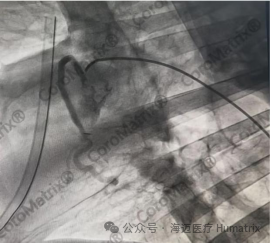

图片

图3 CoroMatrix蔻迈通®人工血管用于羊冠脉搭桥术后DSA随访结果(海迈医疗供图)